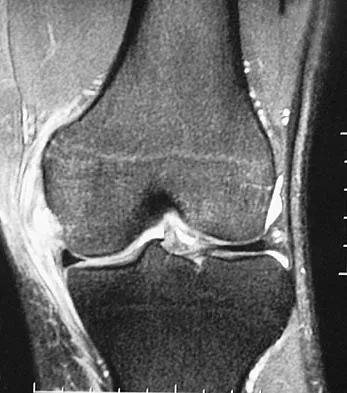

Figure 11 shows a consecutive sequence of MRI scans obtained in a 12-year-old boy who has had increasing lateral knee pain and catching for the past 6 months. Examination reveals pain localized to the lateral joint line. Range-of-motion testing reveals a 5-degree lack of full extension on the involved side. Plain radiographs and laboratory values are within normal limits. What is the most appropriate management?

Figure 24 shows the radiograph of a 10-year-old boy who sustained a valgus injury to the knee. Examination reveals grade III medial laxity. Initial management should consist of